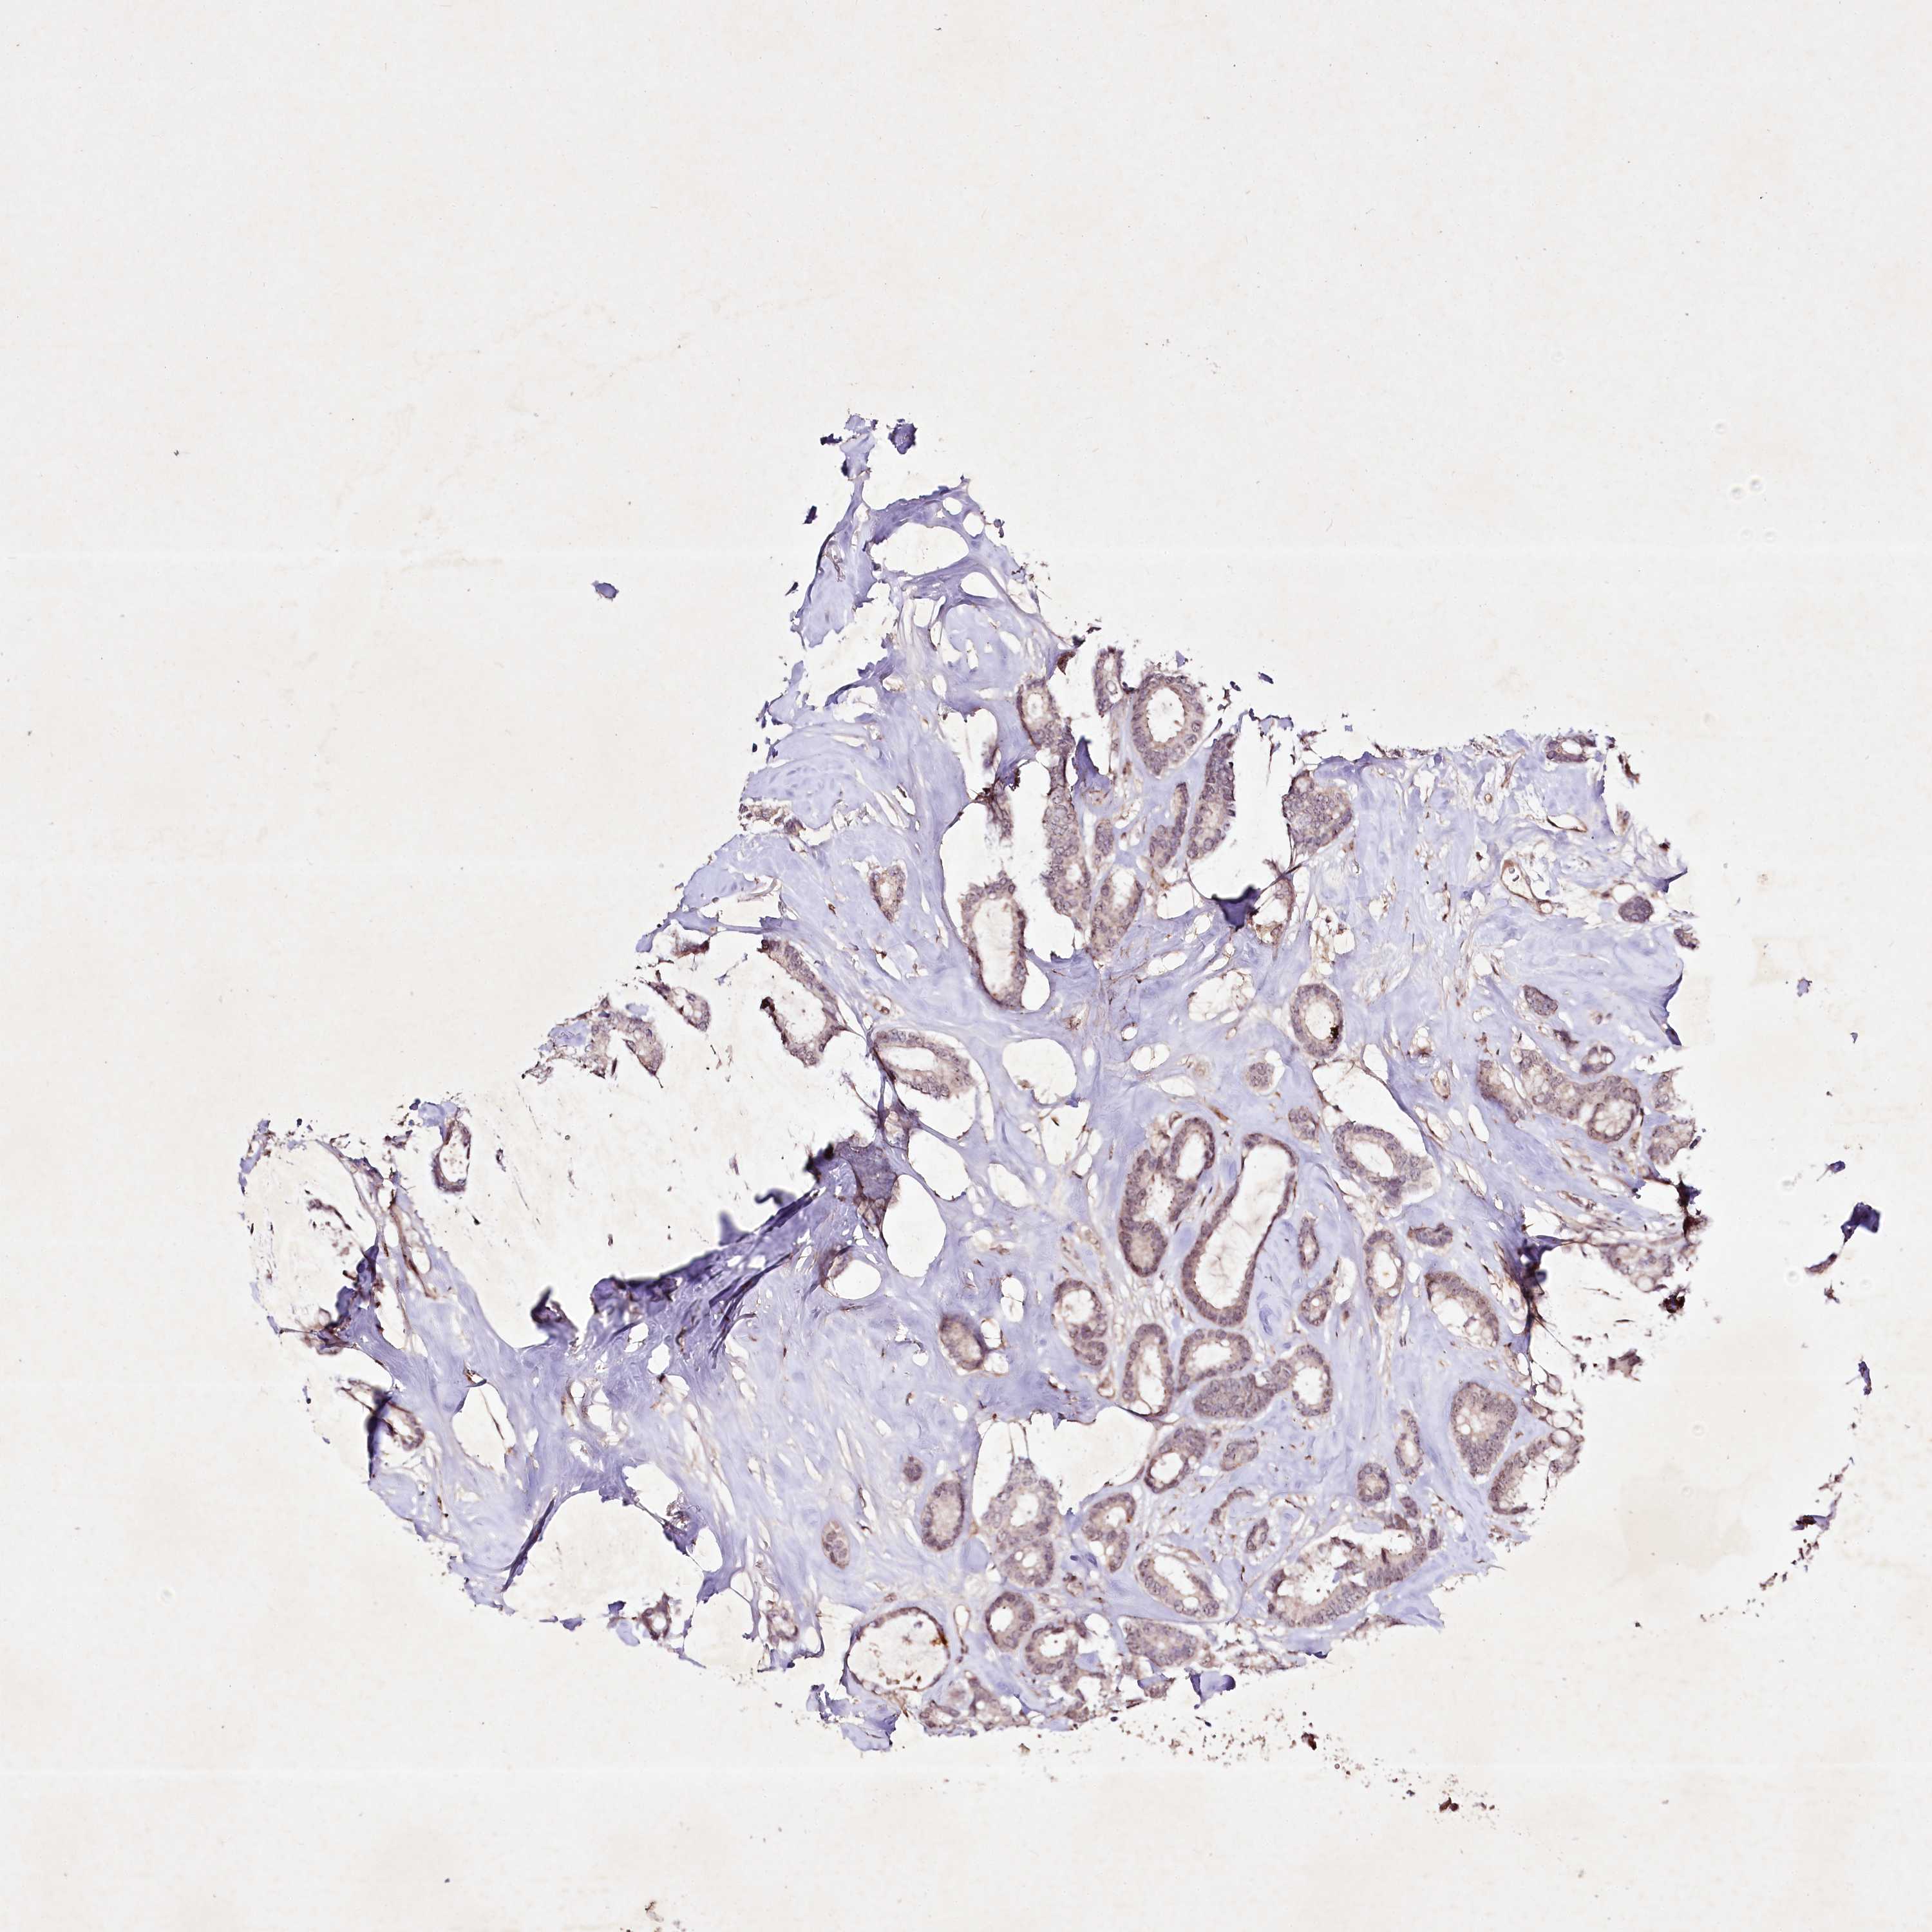

CANCER BREAST CANCER Show tissue menu

BRCA TCGA BRCA VALIDATION PROTEIN EXPRESSION